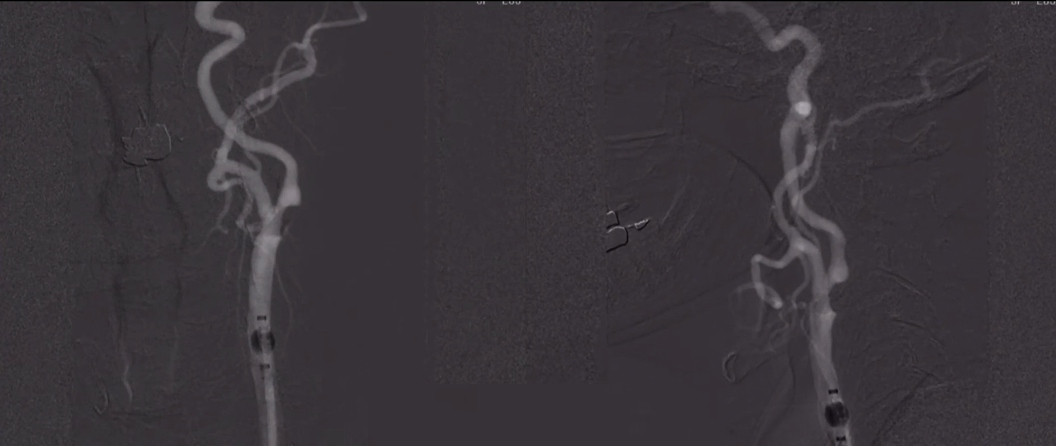

DSA:双侧颈内动脉起始部重度狭窄;前交通及双侧后交通未开放。

8F Fluxcap®球囊导引导管在5FMPA多功能125cm导管同轴辅助下送至右侧颈总动脉,微导丝送至C4段,沿微导丝送入6mm保护伞至C2段平直段,手推造影显示保护伞打开良好。

沿保护伞导丝送入4.0mm×30mm球囊,充盈球囊导引导管的球囊阻断血流,于狭窄段定位后命名压扩张球囊,泄球囊时在球囊导引导管的体外端予以负压回抽血液,取出一2mm血栓。经Fluxcap®球囊导引导管输送7.0-10.0mm×40mm自膨支架(Protégé RX)至狭窄段确认位置后释放。应用125cm多功能导管回收保护伞,多功能导管体外端予以负压回抽血液,保护伞内有血栓。

造影可见残余狭窄10%左右,颅内各分支血管通畅。